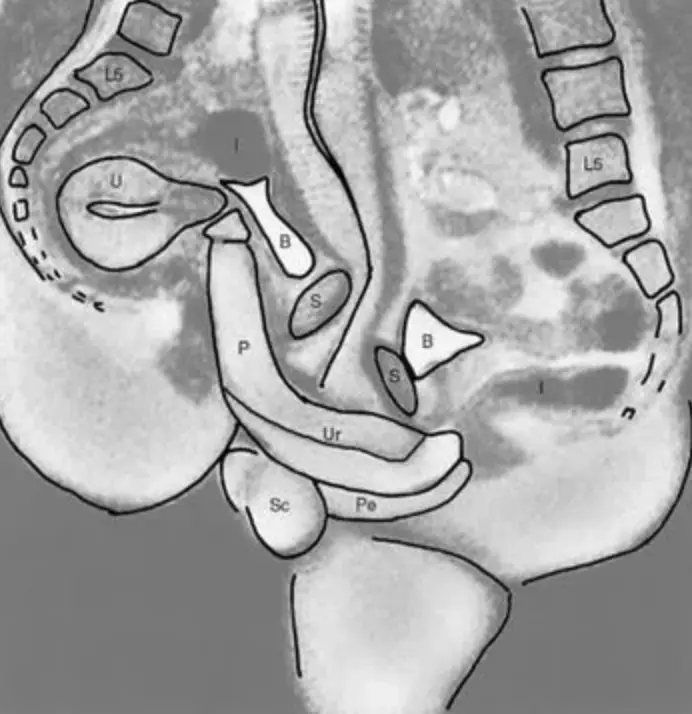

The images, if you want to see them, show two spines as well as genitalia and show exactly how the male and female bodies fit together during sex. If you wanted to study it more closely, there's even a handy key: P=penis, Ur=urethra, Pe=perineum, U=uterus, S=symphysis, B=bladder, I=intestine, L5=lumbar 5, Sc=scrotum.

The photographs, taken during the missionary position, were also useful scientific studies as they showed that the penis isn't straight during in sex but actually curved to fit the natural curve of the vagina.

Also, scientists had previously thought that the uterus expanded during sex but this was proven that despite female arousal, it doesn't appear to get any bigger.